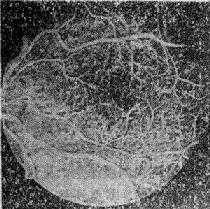

此型特征是在单纯性糖尿病性视网膜病变的基础上,出现新生血管及增殖性病变。脆弱的新生血管易引起反复出血,伴有视网膜纤维组织增殖。新生血管形成是从血管内皮细胞芽开始,可通过内界膜伸展到视网膜表面。视盘前新生血管纤维增殖,通常呈扇形或辐射状伸长,常粘附在玻璃体后面,甚至突入玻璃体中,可导致玻璃体出血和牵拉性视网膜脱离。(表12-2)(图12-11)

图12-11 糠尿病性视网膜病变